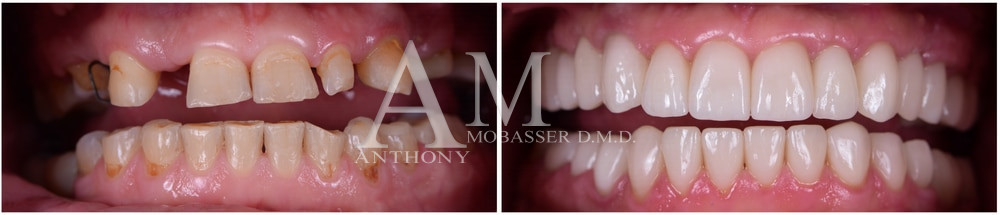

Avant et après la reconstruction dentaire avec Emax Porcelain

Avant et après la reconstruction dentaire pour traiter une supraclusion profonde, à l'aide de facettes en porcelaine et de superpositions de facettes pour ouvrir l'occlusion. La dentisterie esthétique fait partie de la reconstruction dentaire que le Dr Mobasser propose à ses patients à Beverly Hills et Los Angeles CA.

Toutes les cavités radiculaires en bas à droite et en bas à gauche ne doivent pas être traitées en combinaison avec un traitement des gencives, avant de commencer la reconstruction dentaire. Le patient ne pourrait pas être plus heureux grâce au changement de l'occlusion fonctionnelle et à la dentisterie cosmétique réalisée avec la procédure de reconstruction dentaire.

Synopsis : L'imperfection parfaite : Le patient présentait des dents décolorées, des dents fracturées, un ancien collage dentaire devenu brun à jaune, il n'aimait pas la forme de ses dents, il avait des problèmes d'articulation temporo-mandibulaire dus à l'usure de ses dents, il souhaitait une restauration et une reconstruction complètes de sa bouche.

Toutes les dents ont été restaurées, l'occlusion a été réhabilitée, des facettes dentaires en porcelaine ont été utilisées pour reconstruire les dents et l'occlusion. Le patient était très heureux !